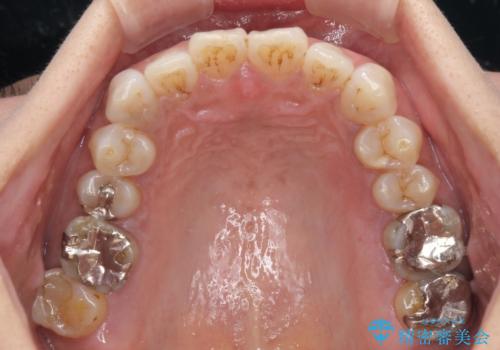

極端な上下前歯の開咬を改善 オープンバイトのインビザライン矯正

- 上下前歯の隙間を気にして来院された患者様です。

開咬の治療は、前歯を閉じるように動かすとともに、上下臼歯を圧下(骨内にめり込ませる)させることで進めて行きます。

インビザラインは臼歯の圧下を効果的に行えるため、インビザラインを用いて矯正治療を行うこととしました。